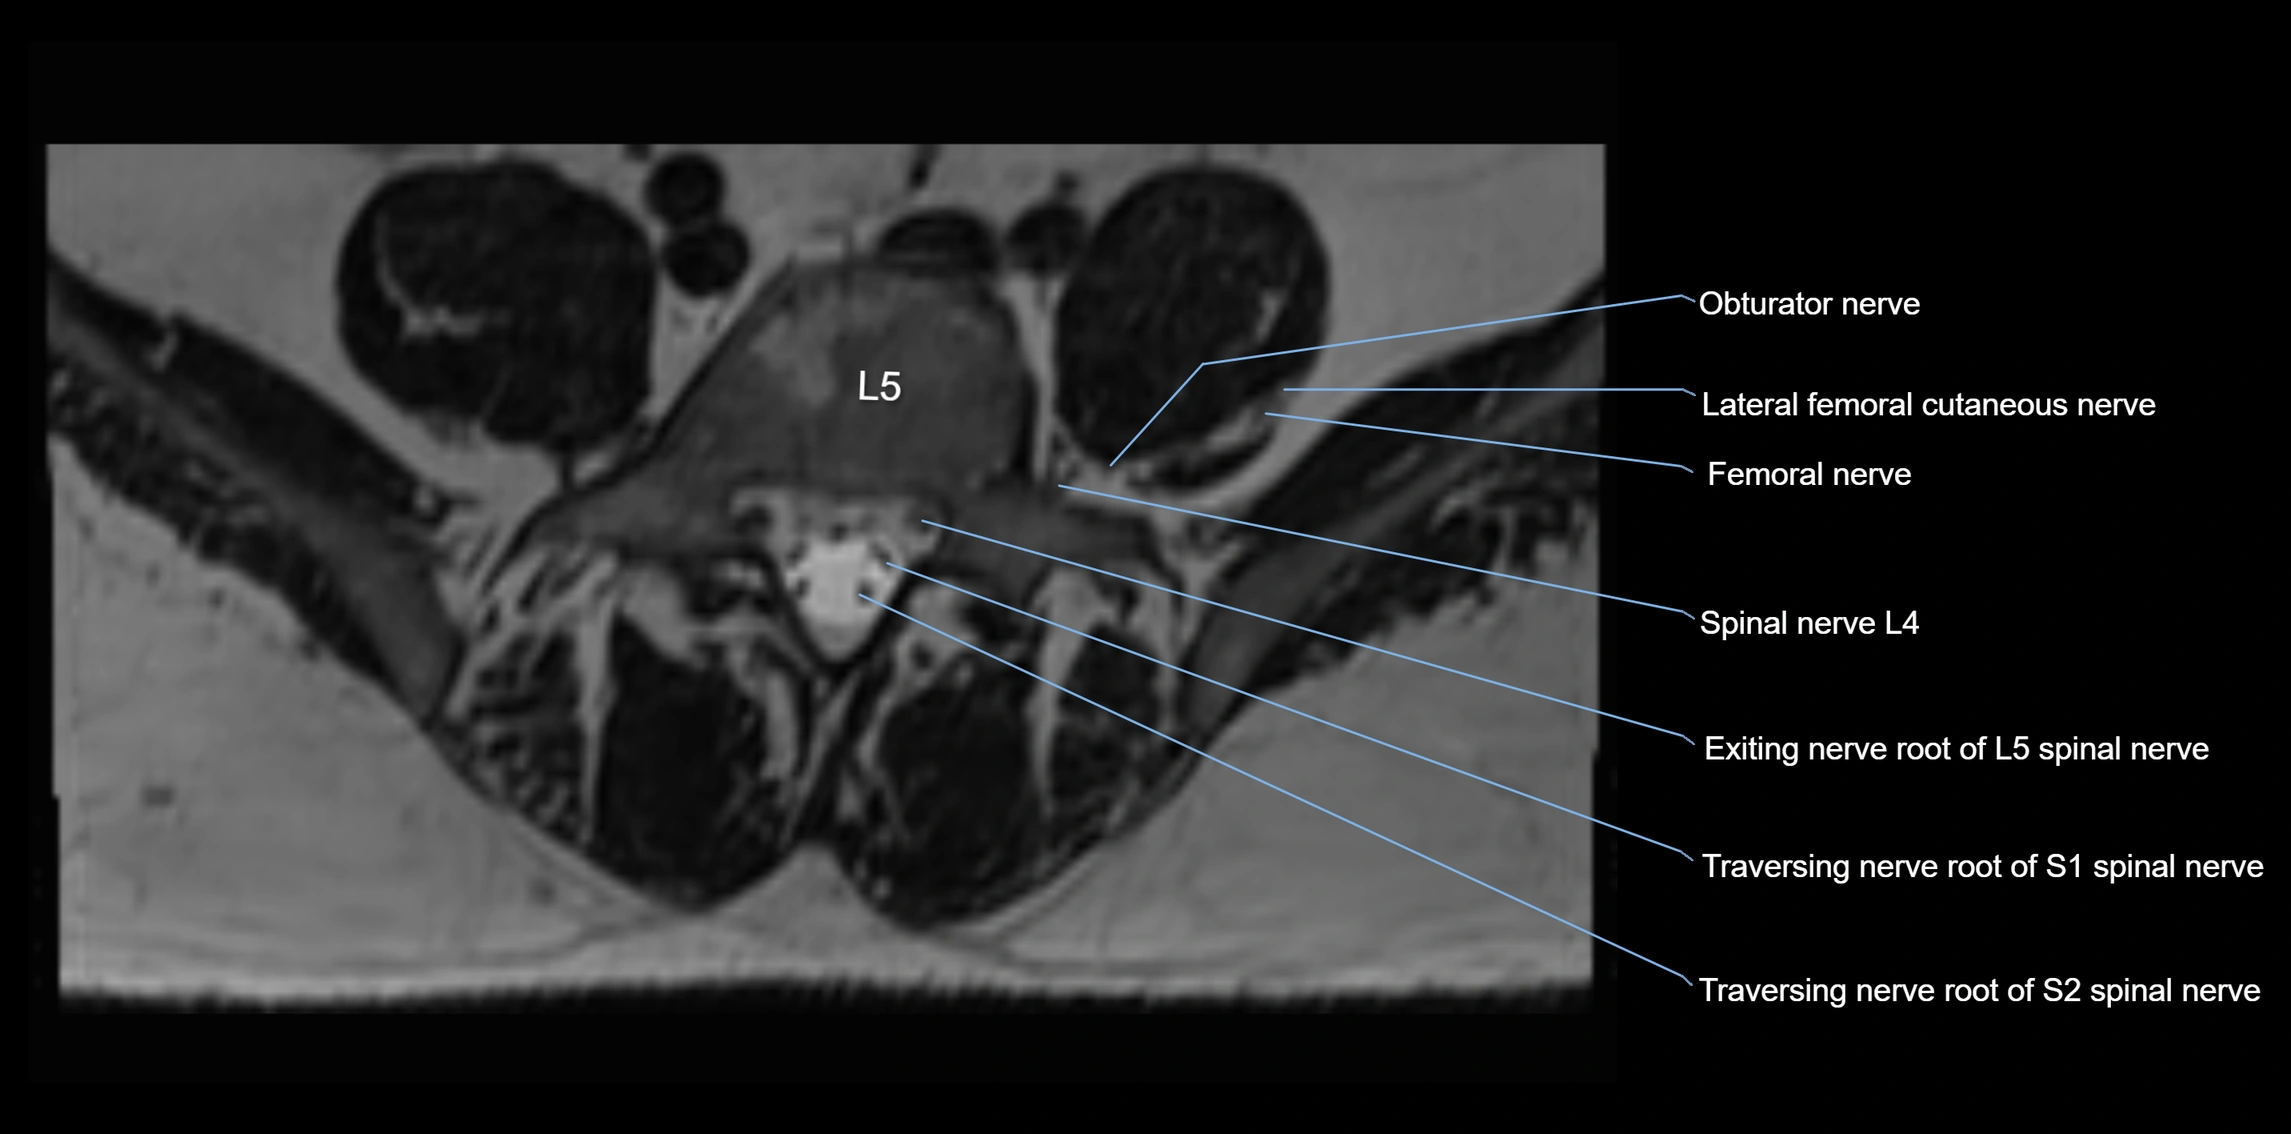

MRI image

image